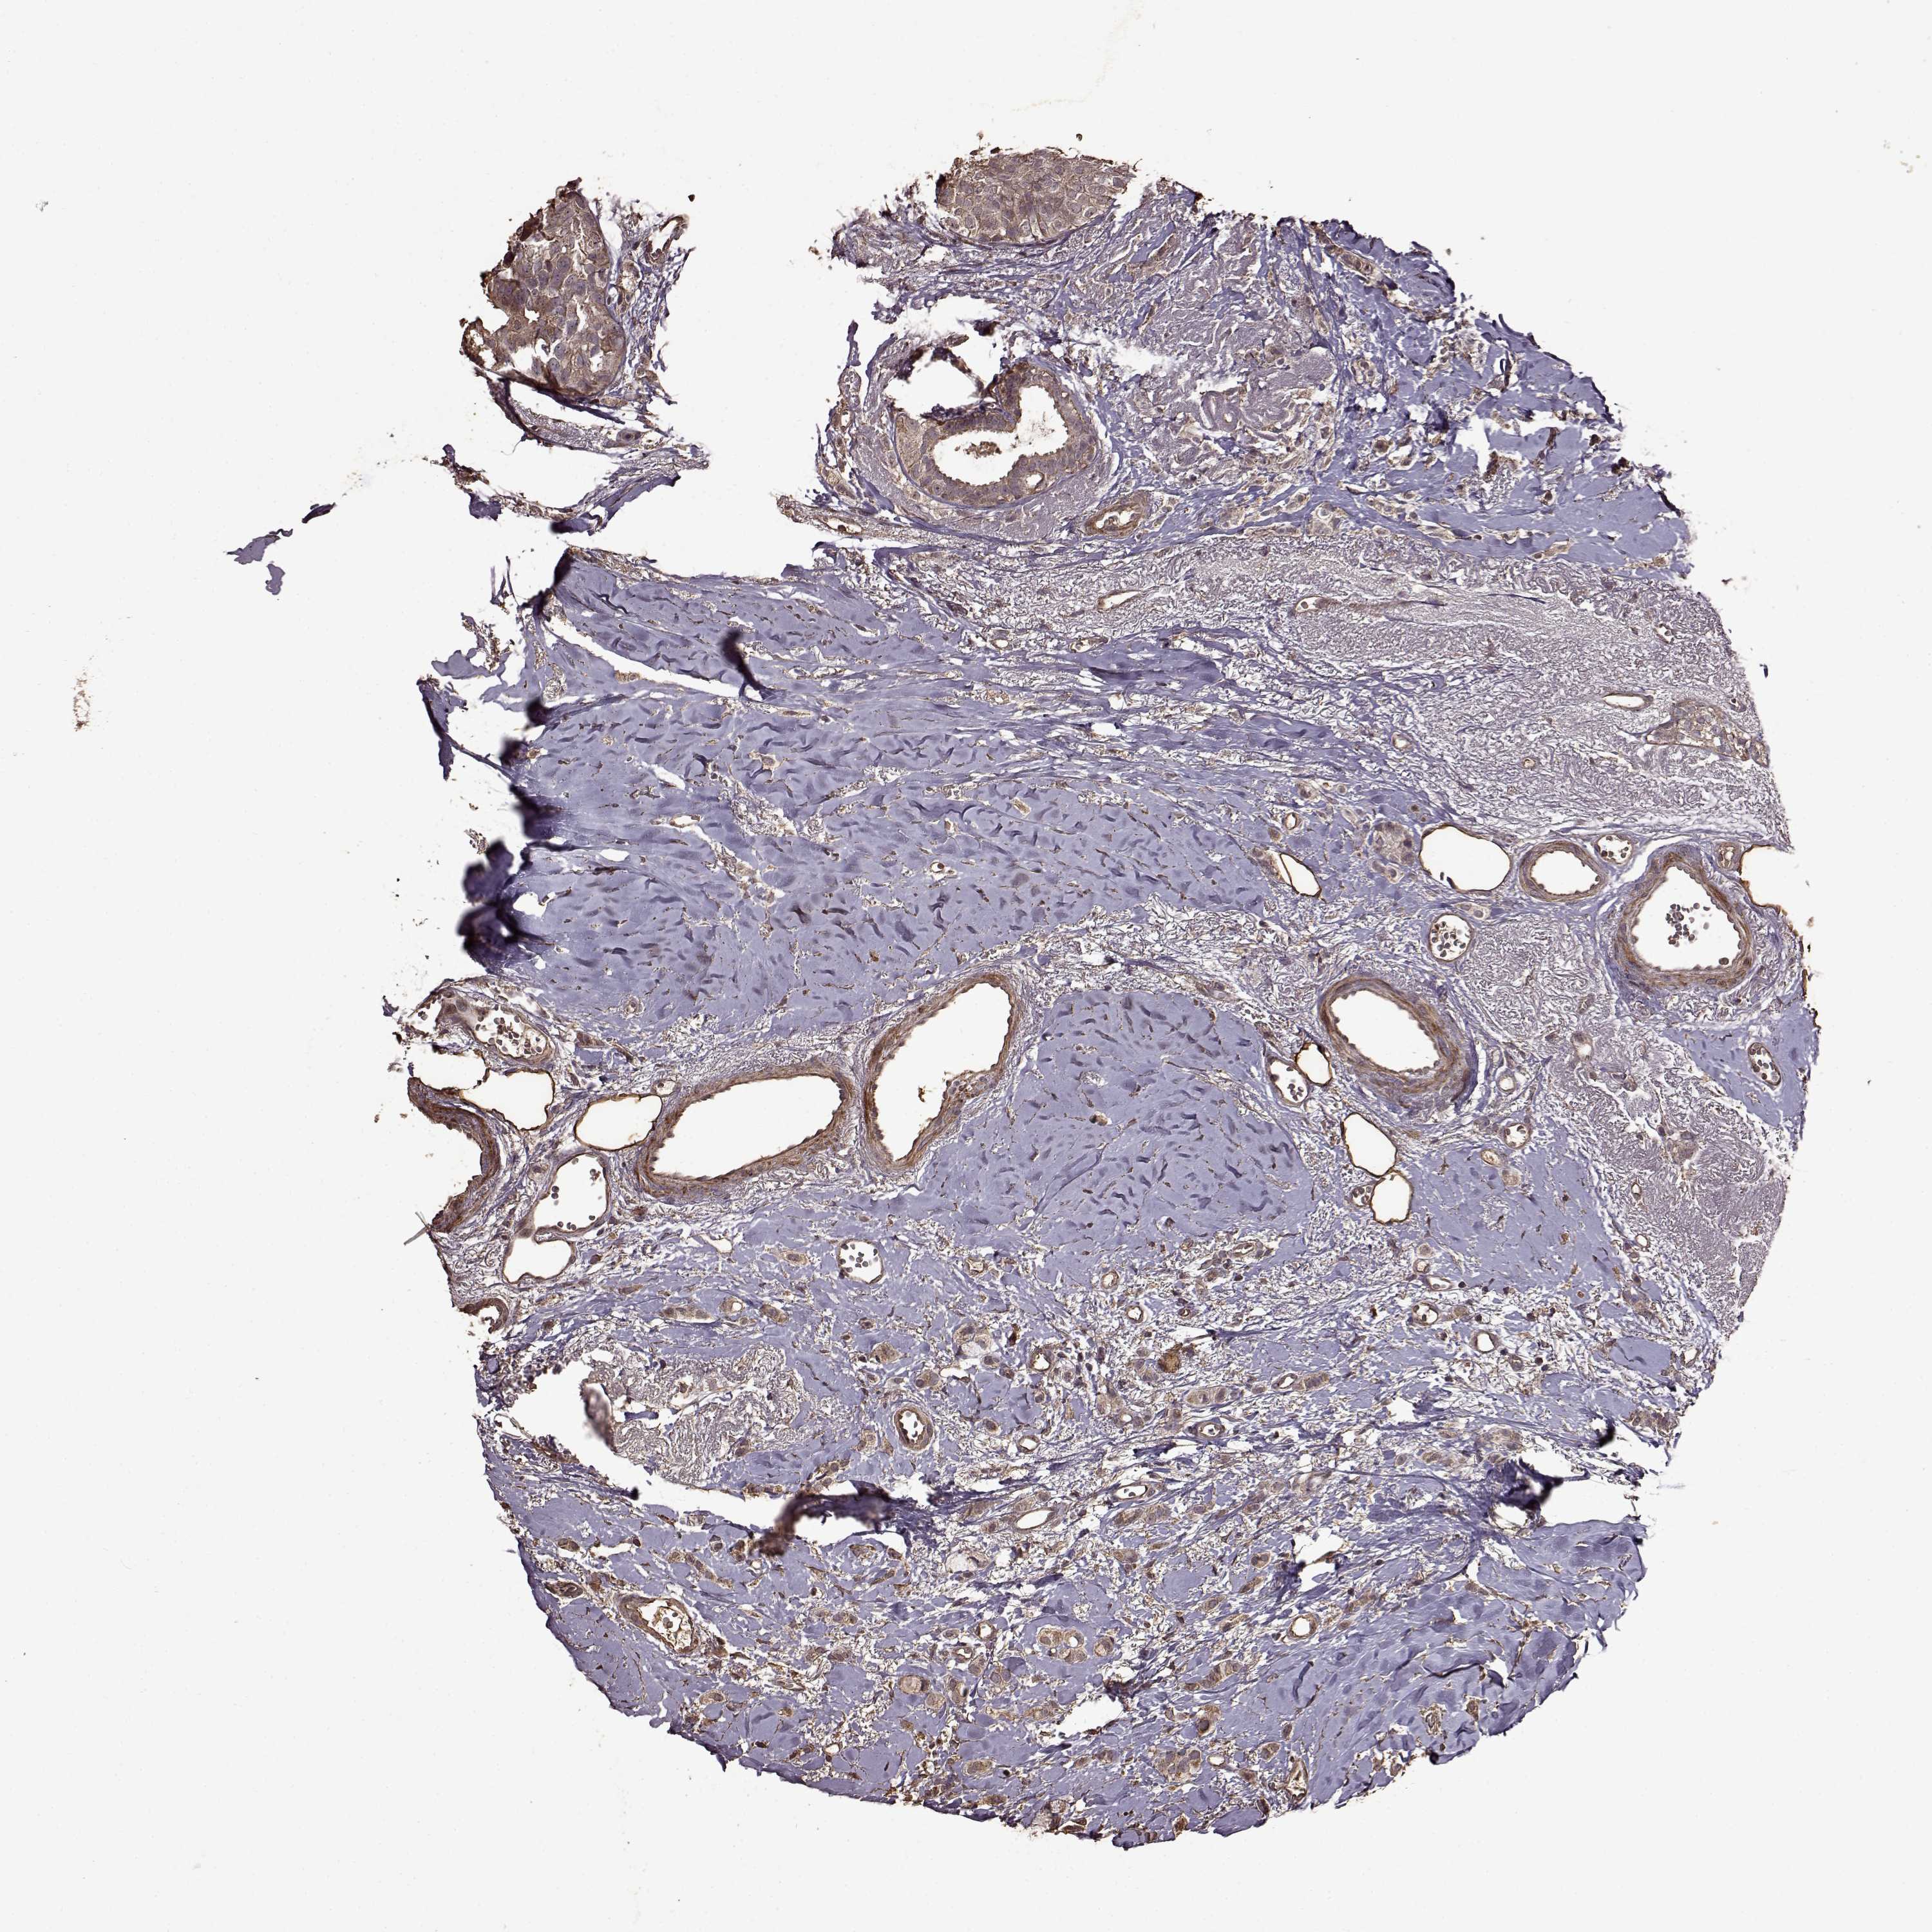

CANCER BREAST CANCER Show tissue menu

BRCA TCGA BRCA VALIDATION PROTEIN EXPRESSION